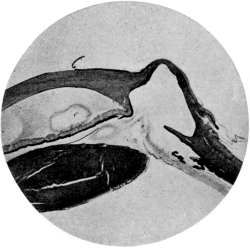

| 110. | The Normal Angle of the Anterior Chamber | 217 |

| 111. | The Angle of the Anterior Chamber from a Case of Recent Glaucoma | 218 |

| 112. | The Angle of the Chamber in a Case of Chronic Glaucoma | 219 |